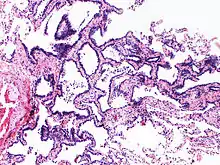

Image histologique de l'hyperplasie adénomateuse atypique.

L'hyperplasie adénomateuse atypique (HAA) est une lésion hyperplasique des pneumocytes bordant les alvéoles pulmonaires et présentant des anomalies cytonucléaires discrètes[1]. Ce terme est préconisé par l'Organisation mondiale de la santé dans sa classification des tumeurs de 2011, puis maintenu et précisé dans les versions de 2015 et 2021. Il caractérise une lésion glandulaire précurseur (précédemment dite lésion préinvasive) de très petite taille[2],[3].

Cette anomalie, de petite taille, inférieure ou égale à 5 mm[3], est une dysplasie, précancéreuse, précurseur de l'adénocarcinome pulmonaire in situ[4]. Le terme de carcinome bronchioloalvéolaire, autrefois employé pour décrire cette lésion est désormais abandonné[4].